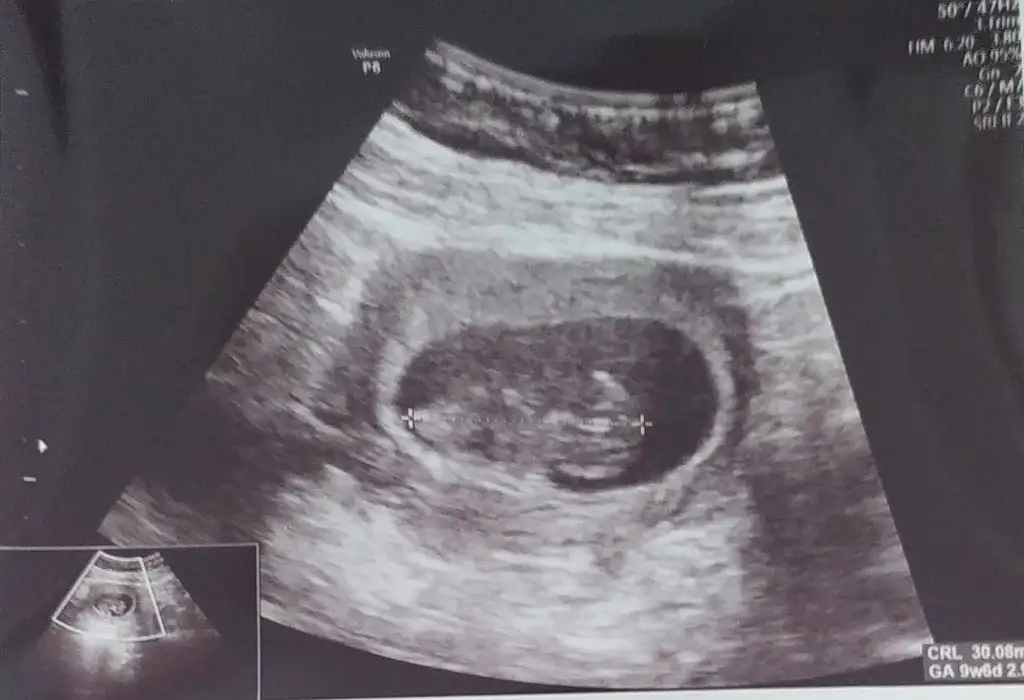

At canım çok şükür kendi iyi olsun da maşallahTam değil kuzucum toplanmış dedi doktorzaten bu doktordan pek bir şey anlayamıyorum açıkçası kendi doktorum ayrıntıyla gösteriyor buna gitme amacim kalbini duymak sağlıklı olduğunu görmekti gripten sonra nasıl diye bir baktık bak atayım hatta

benim tospikte yakaladı mı acaba çok merak ediyorum. ben de 1 hafta geriden geliyordum ya. bakalım bu cumartesi günü doktorumuz ne dicek acaba. şu anda 10+0ım ama aslında 11+0 olmam gerekiyorBu arada bebiş 10+0 çıktı normalde 9+3 tük. Yani sürekli değişiyor şimdilik bir tarih belirlemeyelim böyle olması çok normal ilk 3 ay dedi şimdi de Sat ı yakalamış miniğim.